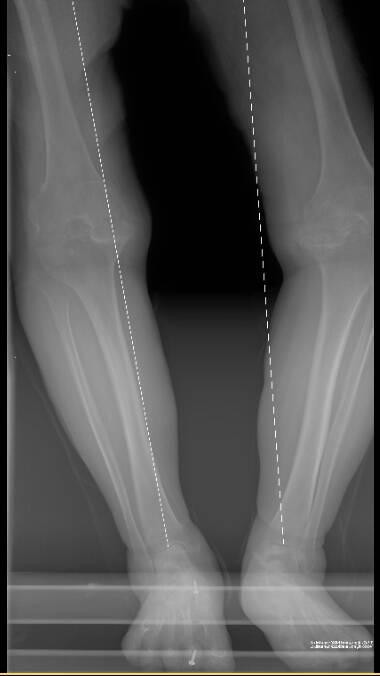

就诊时,孔阿姨的双膝功能损伤严重:左膝屈曲挛缩达-30度,最大屈曲仅90度;右膝亦不能伸直(-20度),屈曲至多100度。经高红伟主任团队详细检查,确诊其为“晚期双膝重度骨关节炎”,关节结构遭受严重破坏,唯有行全膝关节置换术才能有效重建功能、改善生活质量。

全长术前